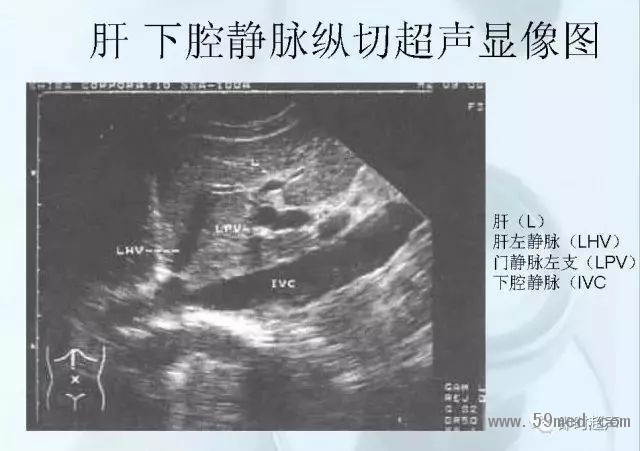

新聞中心 收藏!正常B超解剖圖譜,超實用!